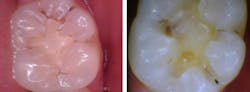

In another case, the Canary System confirmed that an existing composite on tooth No. 18 had mesial and occlusal caries with Canary Numbers 38 and 43, respectively (figure 3).

Figure 3: Tooth No. 18 had mesial and occlusal caries with Canary Numbers 38 and 43, respectively.

Occasionally, new patients become concerned if we discover restorations are needed after checking the teeth with the Canary System but their previous dentists had not found any caries. During one new patient visit, the clinical exam demonstrated a typical virgin pit and fissure (figure 4). The Canary Number was 52, and excavation revealed caries well into the dentin that was not evident on the radiograph.

Figure 4: The clinical exam demonstrated a typical virgin pit and fissure; however, the tooth's Canary Number was 52, and excavation revealed caries well into the dentin that was not evident on the radiograph.